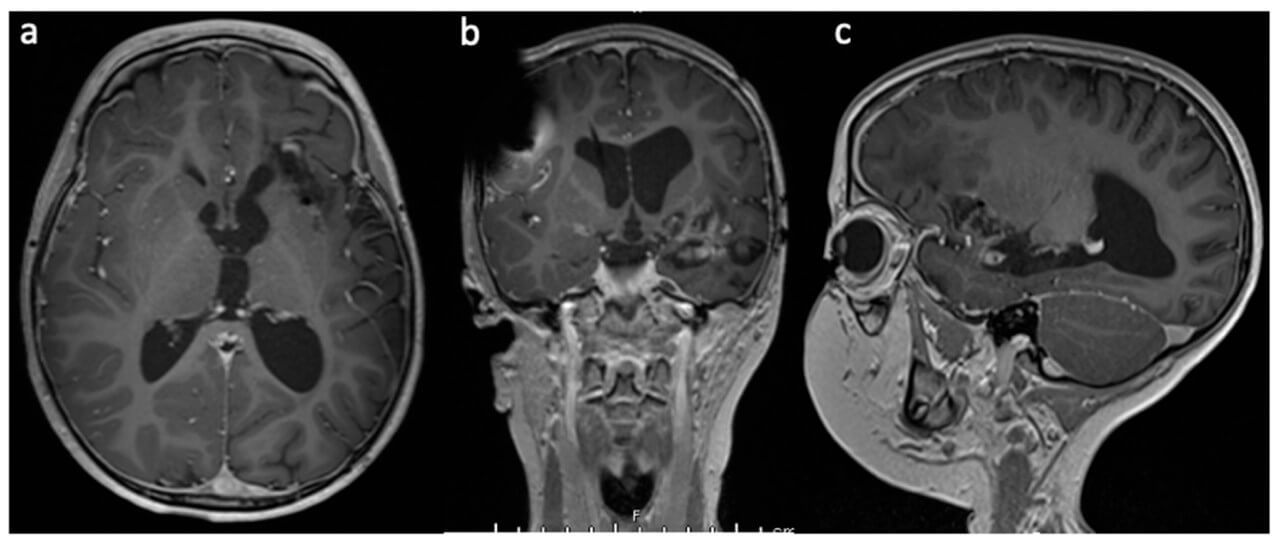

When the catheter reaches the targeted area, the laser inside it starts releasing energy. Due to this, the targeted tissue is gradually warmed up and destroyed. The neurosurgeon monitors the process with the help of real-time MRI scans. Doctors control the intensity and duration of the laser work. Specific MRI thermographic images also show the temperature of nearby tissues – it is substantial for protecting vital regions of the brain.

The increase in the incidence of brain metastases is directly related to the improvement in the effectiveness of modern oncological treatment of primary malignant tumors, which leads to an increase in the life expectancy of patients and, accordingly, to a greater number of secondary lesions of the central nervous system. In this context, thermal ablation is considered a safe and minimally invasive alternative to traditional treatment methods for carefully selected patients.

The Visualase™ system has proven effectiveness in the treatment of various types of tumors, including brain tumors. The use of MRI-guided laser ablation for brain tumor treatment with the Visualase system combines the advantages of this approach with high precision, controllability, and minimal invasiveness, which makes the method particularly valuable in complex clinical cases [5].